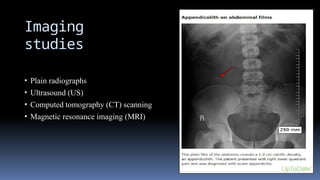

Imaging

studies

• Plain radiographs

• Ultrasound (US)

• Computed tomography (CT) scanning

• Magnetic resonance imaging (MRI)

Imaging studies • Plain radiographs •Ultrasound (US) • Computed tomography (CT) scanning • Magnetic resonance imaging (MRI)